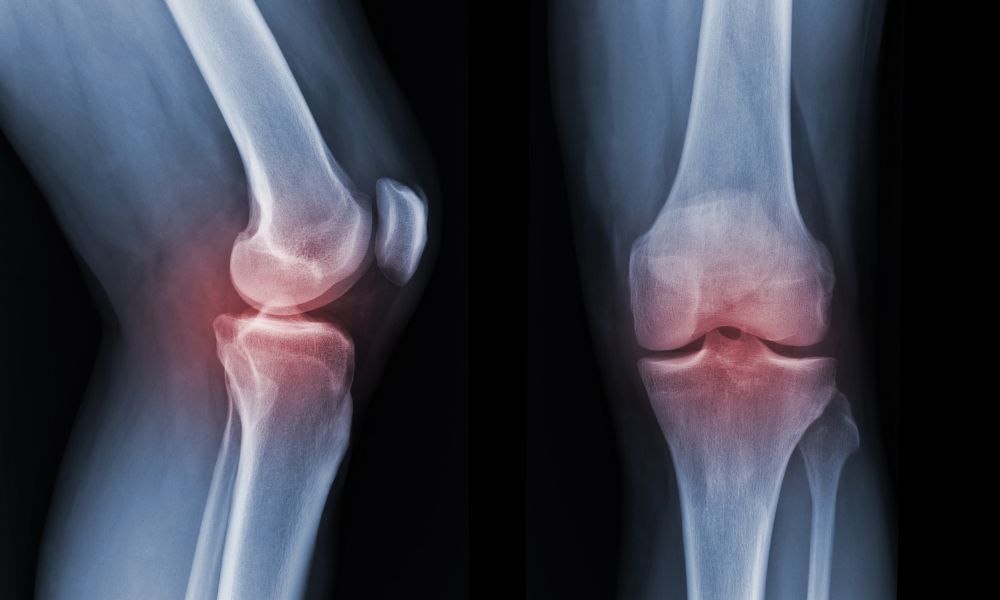

Ich bekam vor 5 Jahren die Diagnose Arthrose.

Die Gelenkschmerzen wurden immer schlimmer – besonders in den Knien und Hüften.

Dann kam die schockierende Diagnose meines Arztes: Arthrose.